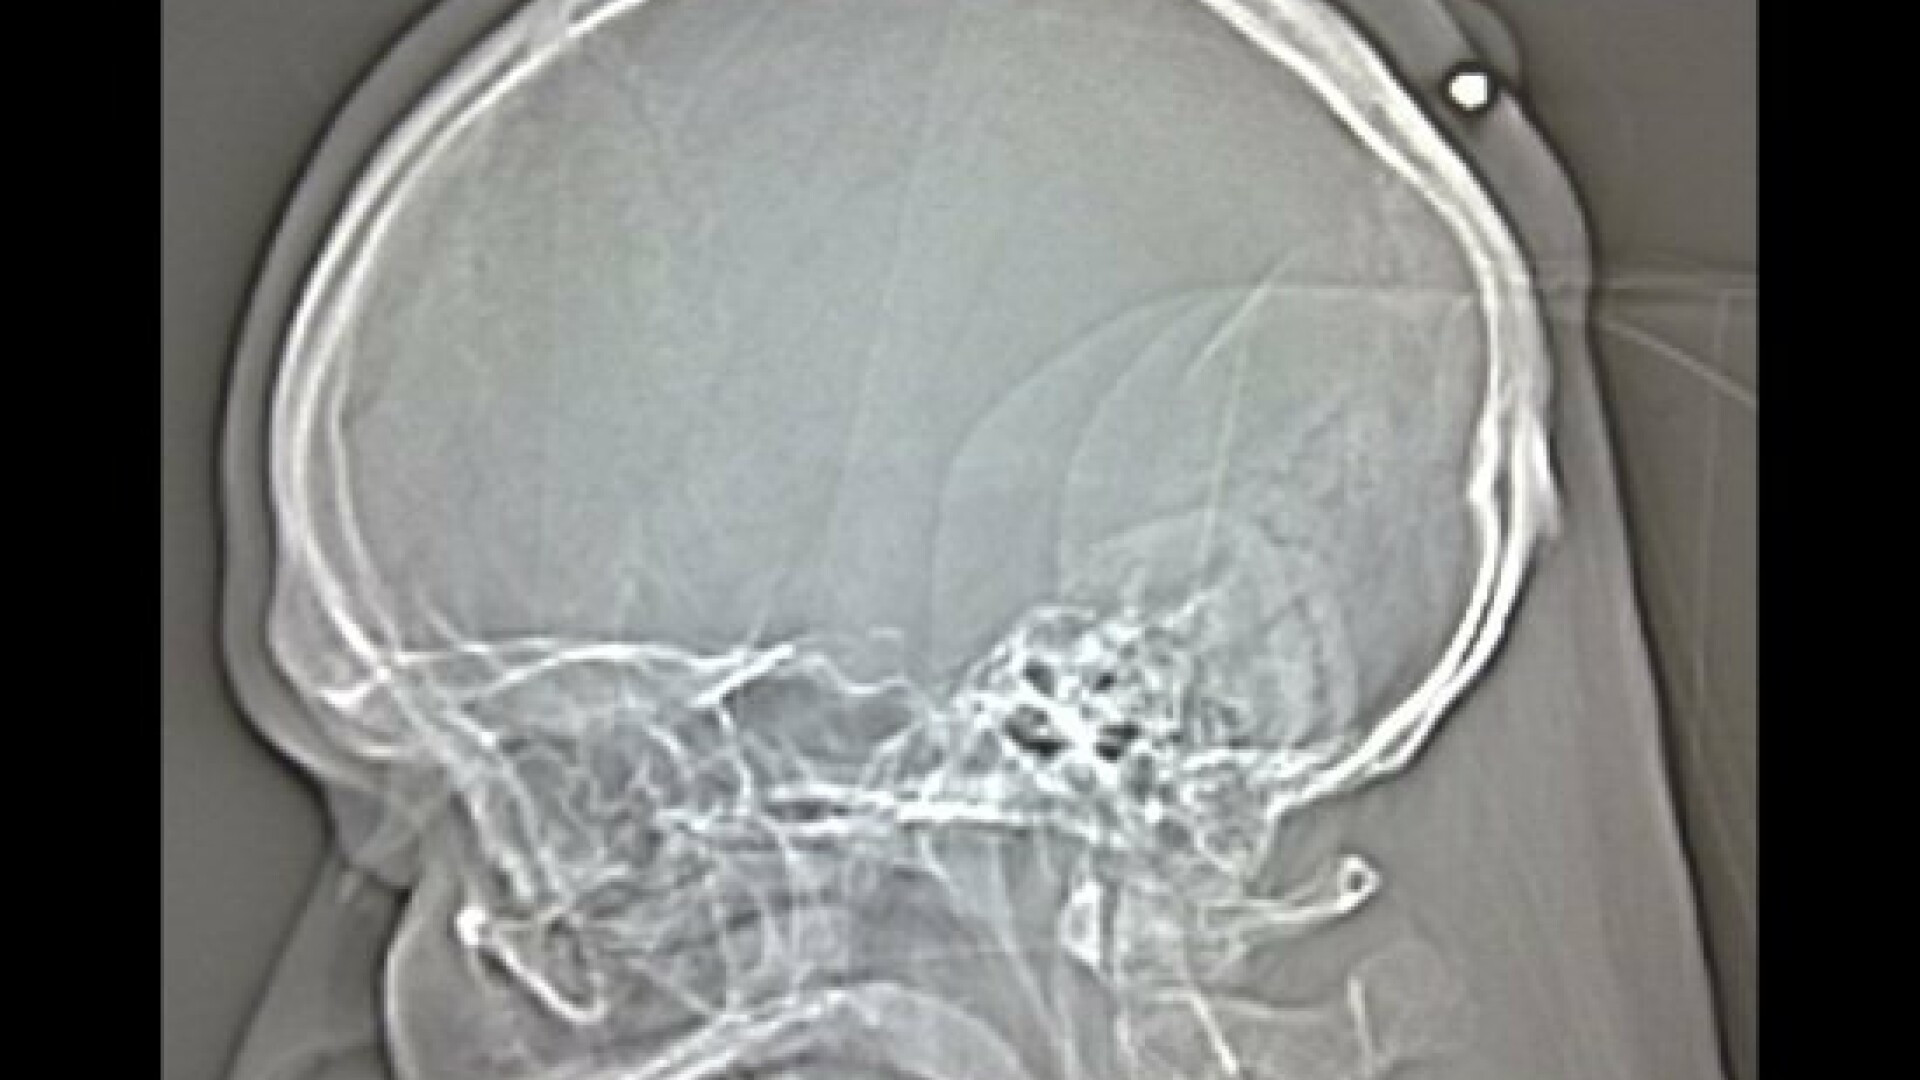

A trait ani de zile cu un glont in cap

Un german a descoperit ca a fost impuscat in cap prin 2004 sau 2005. Constatarea a fost facuta dupa ce un doctor i-a extras glontul, despre care se banuia ca e un chist. Barbatul si-a amintit de incident abia acum, dar a declarat ca, la momentul incidentului, a fost prea beat ca sa mearga la spital.